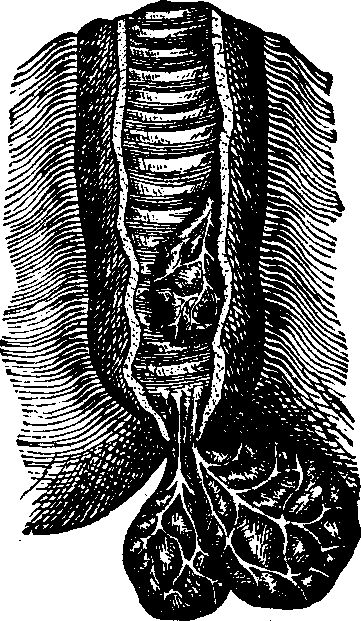

Fig. 7. Vertical section of

cartilage near the surface of ossification. 1. Ordinary appearance

of the temporary cartilage. 1'. Portion of the same more highly

magnified. 2. The cells beginning to form into concentric zones.

2'. Portion more magnified. 3. The ossification is extending

in the inter-cellular spaces, and the rows of cells are seen resting in the

cavities so formed, the nuclei being more separated than above. 3'.

Portion of the same more highly magnified.